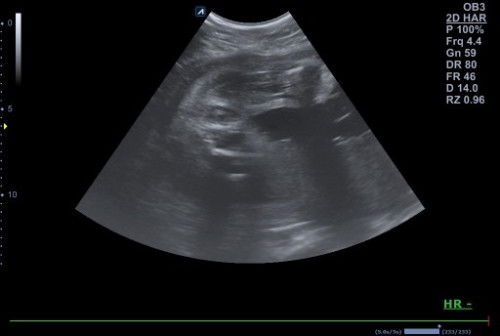

Bun, mau tanya. Ini JK nya cwe ya? Tdi hbis usg cuma dokterny buruยฒ bgt. Jdi butuh kepastian lgi nih

JK dede bayi#mohonbantujawabbunda

kemarin aku gitu juga ,ktnya dokter cewe๐Ÿ˜